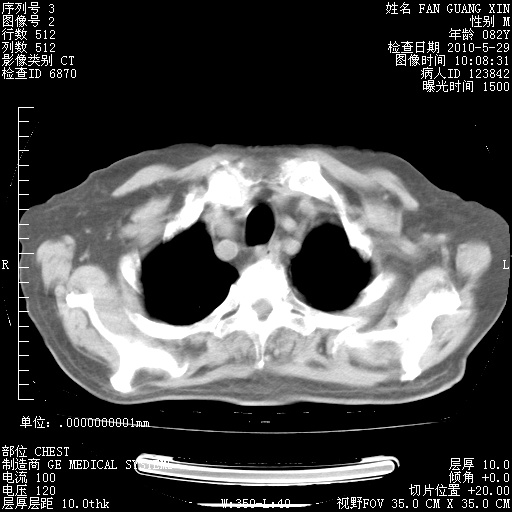

再治疗10天后的肺部CT

再治疗10天后的肺部CT 纵膈窗

肺部体征:呼吸25次/分,心率100次/分,呼吸音增粗。无干湿罗音。

血常规:15.36×10 [sup]9[/sup]/L  N0.92  L0.036  M0.045 ESR 27mm/h。

血生化:白蛋白33.30g/L  球蛋白23.67g/L  CRP 32.82mg/L 肝肾功能正常。电解质正常。

从白细胞总数和中性比例看好像合并感染。肺部纹理好像比上次多,支气管炎?其他感染?

阅读此次胸部CT,肺间质渗出性改变较入院时有吸收。目前从体温、白细胞、中性分叶明显增高,肯定存在细菌感染(发生医院感染哦,若无消化道及泌尿系统等感染的依据,肺部感染可能大)。若你院头孢哌酮舒巴坦钠耐药率较高,同意你的方案,若48小时体温仍高,可考虑使用碳青霉稀类抗菌药物,同时可予超声雾化、注意滴数时加大液体量。白蛋白33.30g/L较低哦,需加强营养等支持治疗。